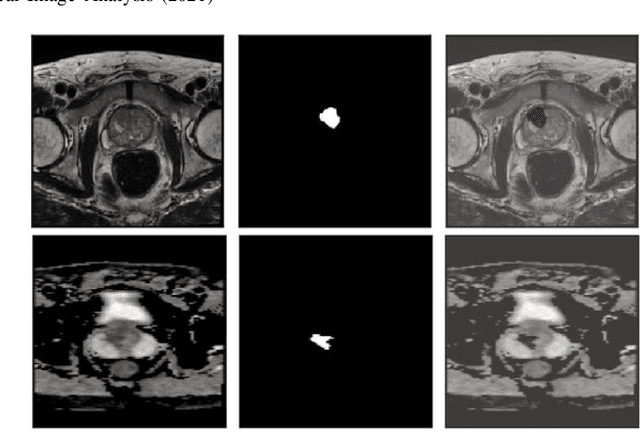

Abstract:Prostate cancer (PCa) is the second most common cancer diagnosed among men worldwide. The current PCa diagnostic pathway comes at the cost of substantial overdiagnosis, leading to unnecessary treatment and further testing. Bi-parametric magnetic resonance imaging (bp-MRI) based on apparent diffusion coefficient maps (ADC) and T2-weighted (T2w) sequences has been proposed as a triage test to differentiate between clinically significant (cS) and non-clinically significant (ncS) prostate lesions. However, analysis of the sequences relies on expertise, requires specialized training, and suffers from inter-observer variability. Deep learning (DL) techniques hold promise in tasks such as classification and detection. Nevertheless, they rely on large amounts of annotated data which is not common in the medical field. In order to palliate such issues, existing works rely on transfer learning (TL) and ImageNet pre-training, which has been proven to be sub-optimal for the medical imaging domain. In this paper, we present a patch-based pre-training strategy to distinguish between cS and ncS lesions which exploit the region of interest (ROI) of the patched source domain to efficiently train a classifier in the full-slice target domain which does not require annotations by making use of transfer learning (TL). We provide a comprehensive comparison between several CNNs architectures and different settings which are presented as a baseline. Moreover, we explore cross-domain TL which exploits both MRI modalities and improves single modality results. Finally, we show how our approaches outperform the standard approaches by a considerable margin